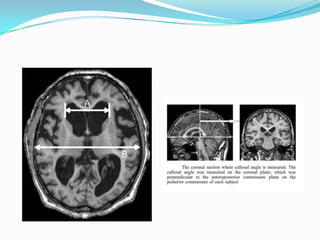

2. Brain imaging

cerebral atrophy or congenital enlargement (Evan’s index

0.3 or comparable measure)

Callosal angle of 40 degrees or more